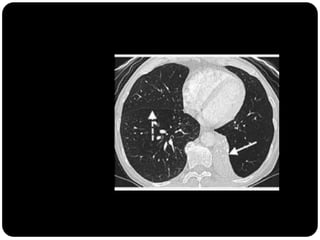

Atelectasia

 Diminuição de volume do segmento, deslocamento de uma ou mais

fissuras interlobares em direção à parte atelectasiada, desvio do mediastino

para o lado envolvido, deslocamento hilar, estreitamento dos espaços

intercostais e hiperinsuflação dos outros lobos / segmentos não atelectasiados

de forma compensatória.

Ex: Colapso do

LSD

Observar

deslocamento de

fissura!

Atelectasia do lobo

superior direito

Atelectasia do Lobo Sup. D.